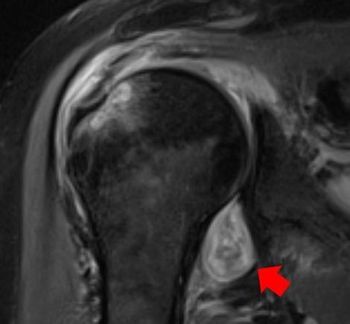

Men with intermediate-risk prostate cancer can be successfully treated with MRI-guided high-intensity focused ultrasound without experiencing incontinence or erectile dysfunction.